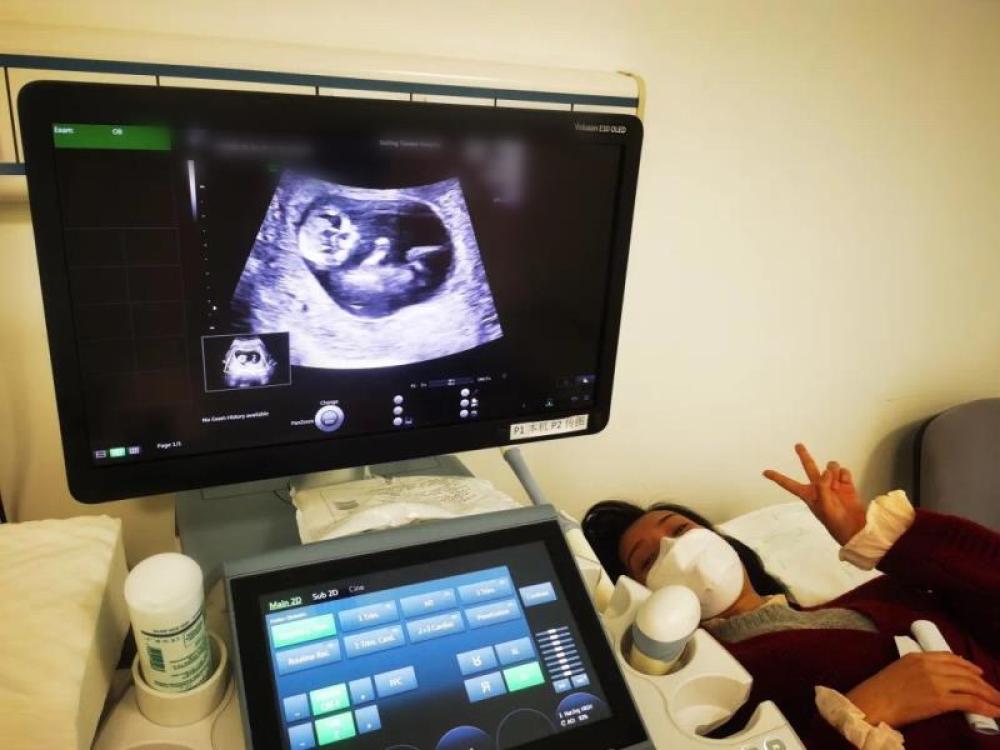

今天一早,妻子去醫(yī)院進(jìn)行B超檢查,同事用手機(jī)拍攝下了B超顯示屏上的畫面,記錄下了這個87天的小家伙第一次“亮相”。

圖為北京天壇醫(yī)院袁磊愛人做B超檢查。

“袁磊,看看你們家寶寶,可愛嗎?”收到同事發(fā)來的視頻,第一眼就看哭了,身邊的同事看完視頻也哭了。

視頻里,這個小家伙好像聽到了外面的召喚,在媽媽的肚子里伸手、踢腿、翻身,用各種動作進(jìn)行回應(yīng)……看到他那小胳膊小腿,一種從未有過的幸福感不停地向上涌,眼淚怎么也控制不住。

其實在武漢這么多天,他一直就是我的牽掛,今天終于看到他了,那種感受真是又緊張又激動,雖然還看不清他的樣子,但是已經(jīng)感受到他的活力。